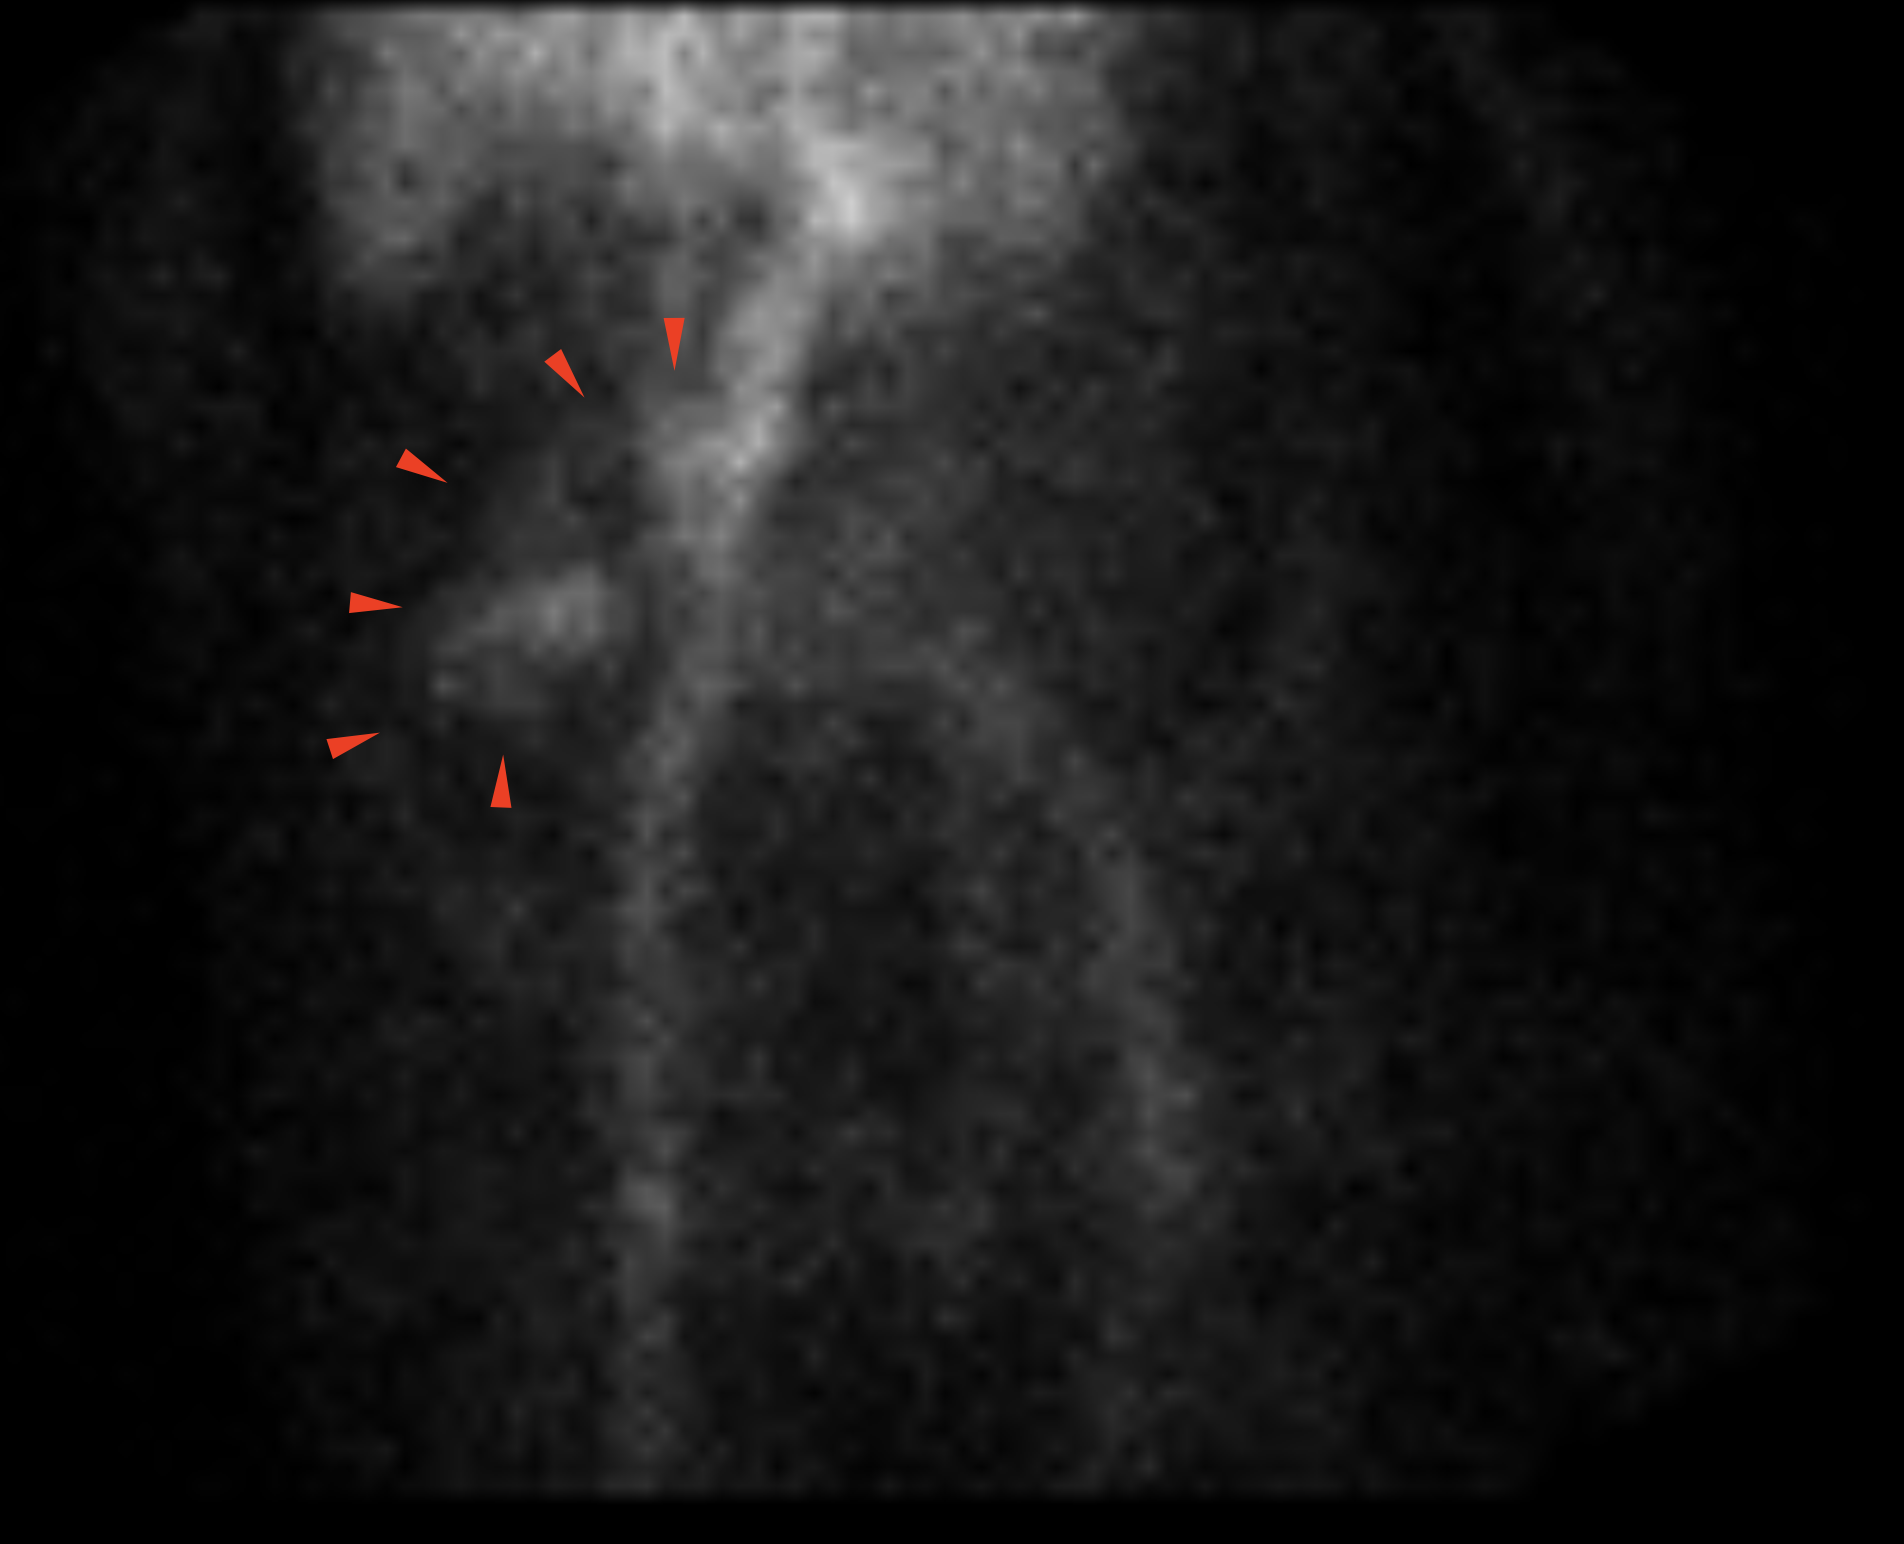

Age: 79

Sex: Female

Indication: Melena

Radiotracer: Tc99m Labeled RBCs

Sample ReportPositive study for active GI bleeding with the origin favored to be in the small bowel.